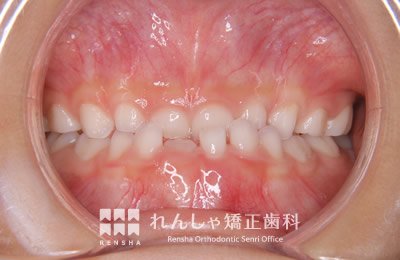

中高生

永久歯列はほぼ完成してしますが、歯列を側方だけでなく後方へも拡大し、埋まっていた右上奥歯を引っ張り出しています。

| 主訴 | 埋まったままでてこない歯がある |

|---|---|

| 診断名 | Angle Class II 小臼歯の埋伏と叢生を伴う上顎前突 |

| 初診時年齢 | 13歳5か月 |

| 装置名 | マルチブラケット装置 |

| 抜歯非抜歯 | 非抜歯 |

| 治療期間 | 2年3か月 |

| 費用の目安 | 約82万円+消費税(検査料金、都度の処置費用等も合わせた総額) |

| リスク副作用 | 歯の移動に伴う軽微な歯根吸収、歯槽骨吸収、歯肉退縮(本症例では軽度の歯根吸収を認めた)、矯正器具装着中のカリエスリスク増大(本症例ではカリエス発生無し) |